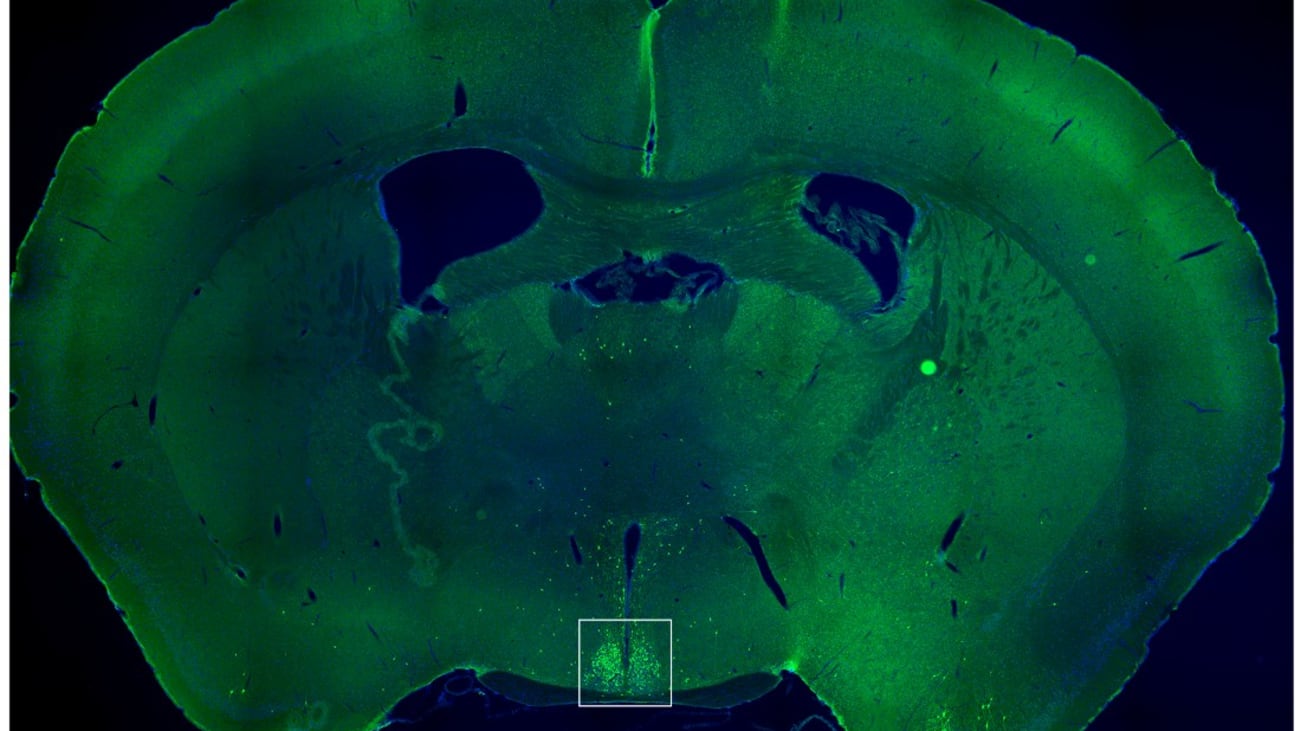

This image shows a thin slice from the middle of a mouse brain, with the region known as the suprachiasmatic nucleus (SCN) surrounded by a white box. The small green dots mark brain cells that react to the hunger hormone ghrelin. When the ghrelin-sensitive cells in the SCN are turned off during the mouse’s normal rest time, the animals snack less and lose weight.

Activating specific neurons in a part of the brain that serves as the body’s master circadian pacemaker caused mice to eat significantly more during a time of day when they would normally be at rest, a UT Southwestern Medical Center study shows. The findings, published in Cell Reports, could lead to new strategies to help people lose weight, including night shift workers who have a higher prevalence of obesity.

These observations suggest specific circuits of neurons that affect feeding and metabolism might operate differently at various times of the day. Dr. Zigman, Dr. Singh, and their colleagues hypothesized that one such circuit might be in the suprachiasmatic nucleus (SCN), a part of the brain that sets circadian rhythms throughout the body based on light received through the eyes.

Previous research in the Zigman Lab showed that some SCN neurons are stimulated by ghrelin, a hormone that prompts feeding and slows metabolism to encourage weight gain. However, the significance of these findings had been unclear.

To better understand this population of SCN neurons, the researchers worked with mice genetically altered so the scientists could turn these neurons on and off. They found that if they turned on the neurons in the middle of the animals’ rest period – around 10 a.m., since mice are nocturnal – they ate more than two times as much as they usually do during this time. Turning the neurons off at this time reduced the already low amount of food typically consumed during this period.